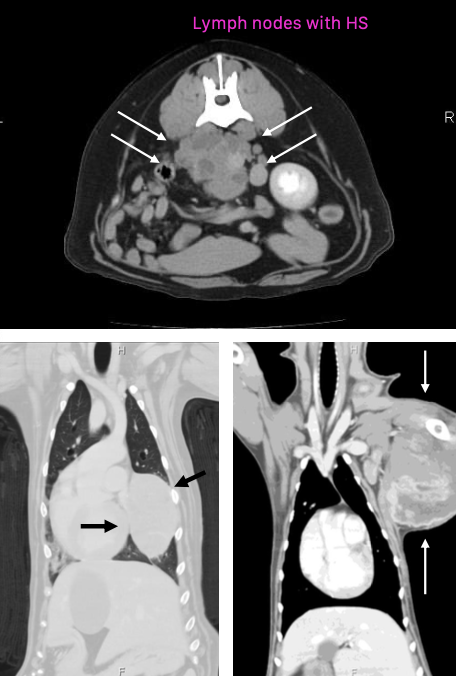

what is disseminated histiocytic sarcoma?

aka malignant histiocytosis

aggressive, with multiple sites of involvement

what are the anatomic predilection sites for disseminated histiocytic sarcoma?

-multi-organ

-LNs, liver, lung, spleen most common